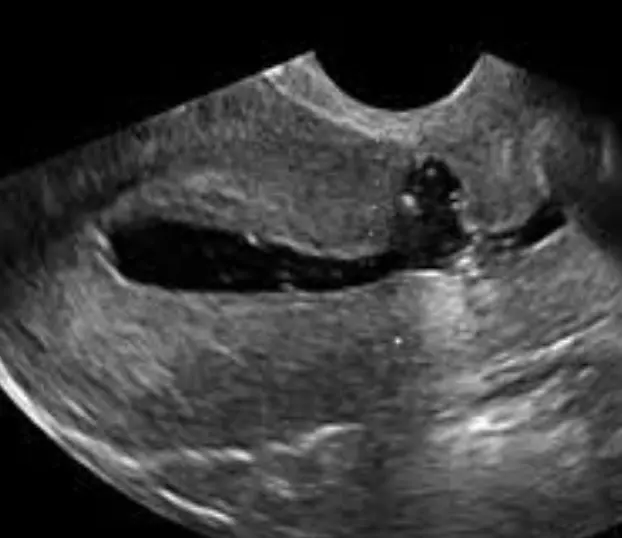

Ovaries: The scan assesses the size and presence of cysts. During the assessment, we will assess the number of antral follicles and follicle sizes.

Assessment for Endometriosis: an assessment for evidence of Endometriosis is performed in all gynaecological ultrasounds.